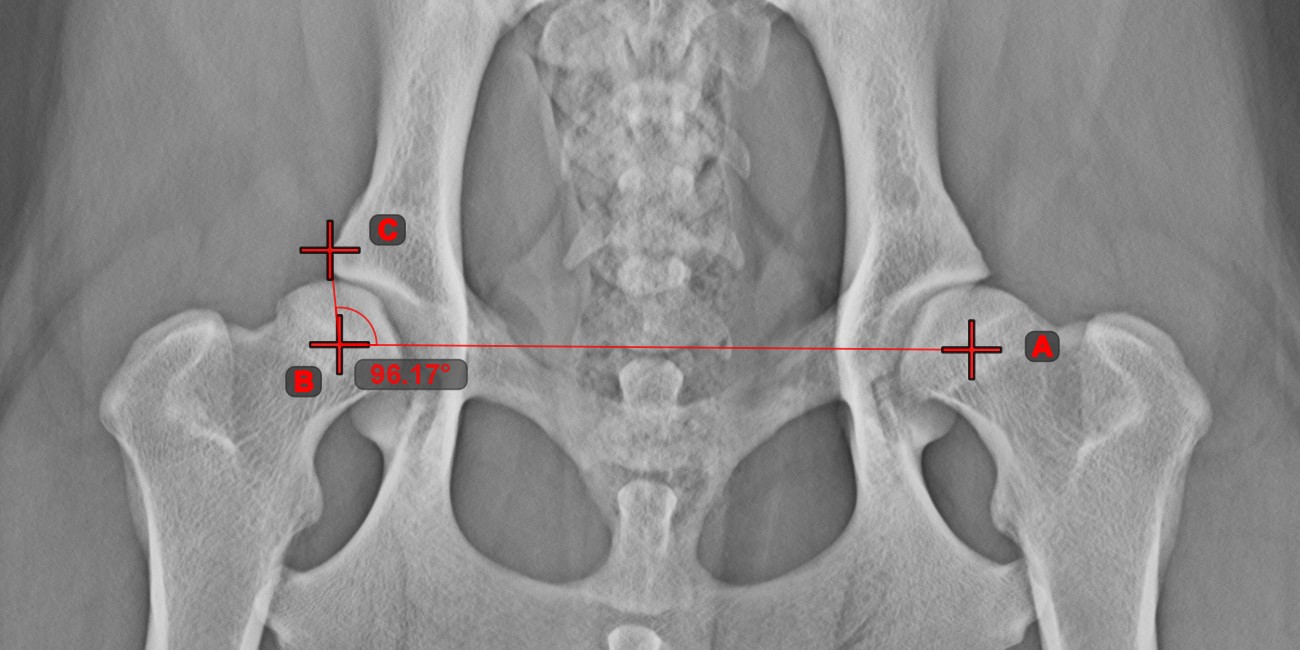

Winkel aus 3 Punkten¶

Das Werkzeug Winkel aus 3 Punkten ist eine einfache und effektive Möglichkeit, einen Winkel anhand von nur drei Punkten zu berechnen.

Beginnen Sie, indem Sie das Werkzeug aus der linken Symbolleiste auswählen und einer der verfügbaren Maustasten zuweisen. Setzen Sie den Startpunkt der Anfangsseite, den Scheitelpunkt und den Endpunkt der Endseite des Winkels oder wählen Sie die Punkte aus der Szene aus. Die Seiten des Winkels werden automatisch konstruiert, wodurch der Winkel zwischen den Linien berechnet wird.

Ändern Sie die Position der drei Punkte, um den Bogen des Winkels mit dem Werkzeug Objekt auswählen/verschieben zu ändern.